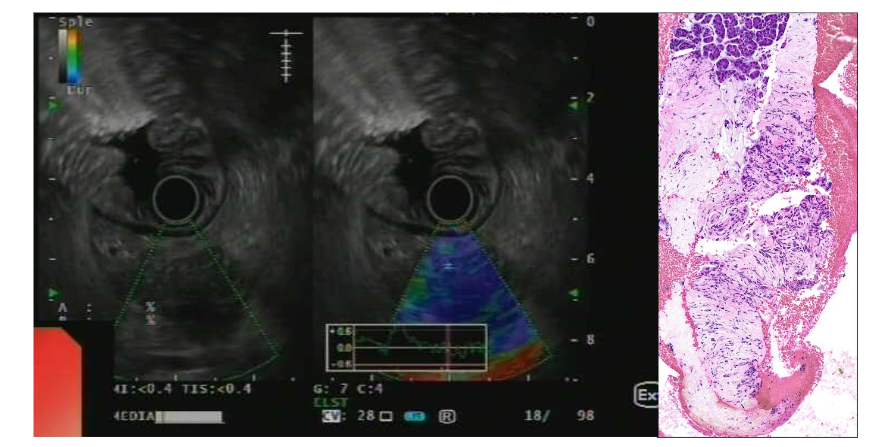

Imaging studies play a crucial role in localizing and characterizing PNETs. Contrast-enhanced CT and MRI can define the size, location, and vascularity of the tumor, which can help with therapeutic management and prognosis. MRI is similar to CT in detecting PNETs; they appear as round hypointense lesions on T1 and hyperintense compared with pancreas on T2-weighted images¹⁶. Functional imaging with somatostatin receptor scintigraphy (SRS) or 68Ga-DOTATATE PET can identify tumors expressing somatostatin receptors, thus facilitating targeted treatment options with somatostatin analogs. Finally, EUS contributes to the histological confirmation of the diagnosis using elastometry studies (Figure 2) and provides histological material to assess the histological grade and stage of the PNETs²⁷˒²⁹˒³³.

Microscopically, PNETs are well-differentiated tumors. They exhibit characteristic architectural patterns, including nested, trabecular, or glandular growth, and express neuroendocrine markers such as chromogranin A and synaptophysin. Based on their proliferative activity, PNETs are graded from G1 to G3³⁴. Unlike their pulmonary counterparts, neuroendocrine carcinomas (NECs) of the pancreas are rare³⁵.

Figure 2. EUS imaging showing a pancreatic neuroendocrine tumor with a low strain ratio. Biopsy reveals monomorphic neoplastic cells with minimal atypia in trabecular pattern. The stroma is minimal, richly vascular with fine, capillary-sized vessels (H&E, 200x). Neoplastic cells express chromogranin A and synaptophysin with a slightly elevated Ki67 proliferation index (Ki67 immunostaining, 200x).